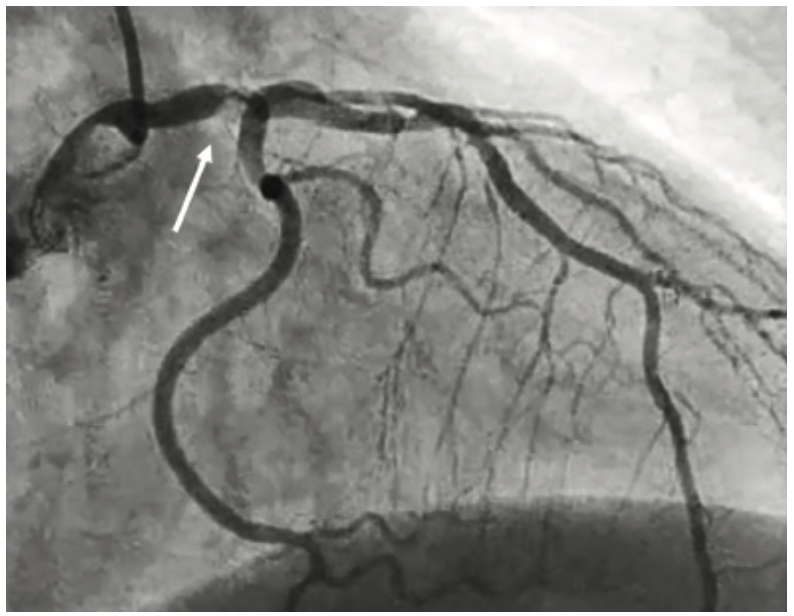

Hypotension After Coronary Injection

Hypotension after a coronary contrast injection is an early warning sign of trouble. For the right coronary artery (RCA), a vagal response (low BP, low heart rate) would be common and is transient. For the left coronary artery, hypotension can herald danger, with the most immediate life-threatening event being left main (LM) obstruction due to dissection, thrombus, or spasm (Figure 1). A LM ostial stenosis is detected by pressure damping on the coronary angiogram, which takes on a ventricular-like wave pattern (Figure 2). Removal or readjustment of the catheter is important to discriminate between non-coaxial malalignment of the catheter tip and true LM narrowing. In patients with LM disease, forceful injections or catheter manipulations with plaque disturbance may cause acute myocardial ischemia due to closure of the vessel. Hypotension during coronary angiography associated with ST segment changes is indeed a life-threatening emergency that requires emergent evaluation, and possibly angioplasty or bypass surgery.